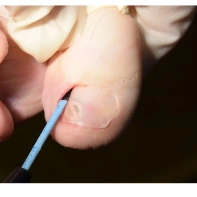

- Хирургическое иссечение. Под местной анестезией при помощи скальпеля удаляется вросший край ногтевой пластины вместе с зоной роста, затем на рану накладываются швы. В некоторых ситуациях вместе с резекцией ногтя проводится пластика околоногтевого валика, позволяющая повысить эффективность оперативного вмешательства и добиться стойкой ремиссии заболевания.

- Лазерная резекция. Лазером удаляется вросший кусочек ногтя и поврежденные слои ногтевого валика. Затем прижигается разросшийся участок ростковой зоны. При этом лазерные пучки одновременно стерилизуют ногтевое ложе, исключая риск развития инфекционных процессов и ускоряя процесс заживления. Операция занимает 15–20 минут, имеет минимальную травматичность. Период восстановления после такого вмешательства относительно короткий.

- Подготовка к процедуре, включая местную анестезию.

- Непосредственное удаление патологически измененных тканей.

- Обработка раны и наложение стерильной повязки.

Лечение вросшего ногтя СО2-лазером

Пациентам с обострением вросшего ногтя, который беспокоит длительное время, может быть показано выполнение краевой резекции СО2-лазером. Облегчение и снижение болевого синдрома наступает непосредственно после вмешательства. Подробнее об операции рассказывает хирург-онколог Георгий Исаевич Исмаилов.